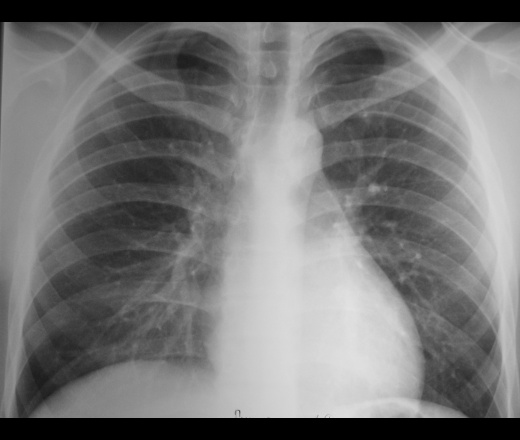

Рентген грудной клетки

Рентген грудной клетки помогает выявить проблемы с сердцем и легкими. Рентгенограмма грудной клетки слева в норме. На изображении справа показано образование в правом легком.

Рентген грудной клетки позволяет получить изображения сердца, легких, кровеносных сосудов, дыхательных путей, костей грудной клетки и позвоночника.

Рентген грудной клетки также может выявить жидкость в легких или вокруг них или воздух, окружающий легкое.